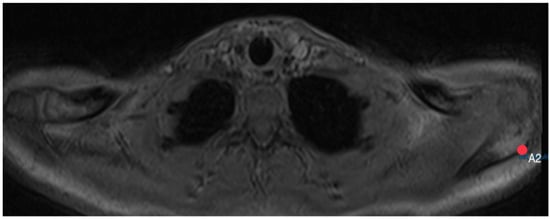

2.3. Acromion Index (Figure 1)